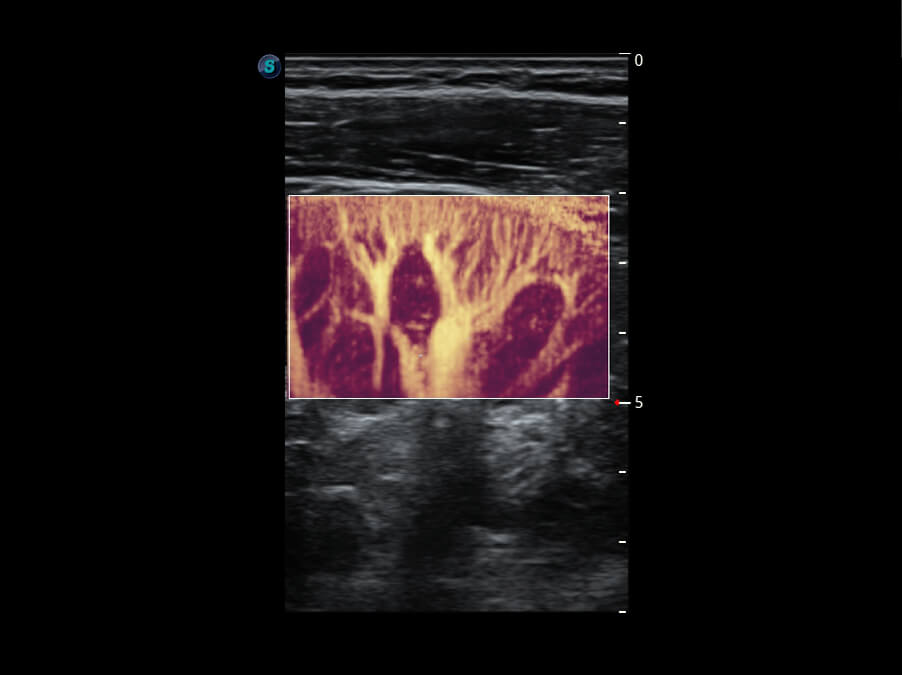

S60探头工艺,从前端信号处理每一个环节采集无损声学数据,真实还原组织原貌,再现解剖细节。